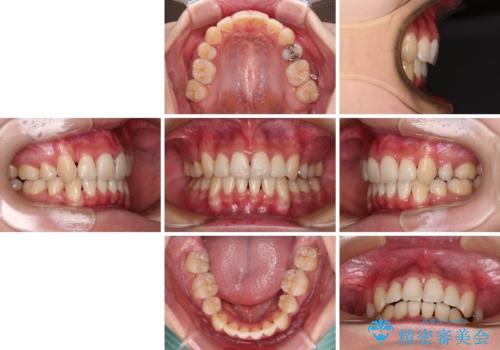

前歯の歯並びを治したい ワイヤー装置での抜歯矯正

- 前歯の叢生と八重歯を気にして来院された患者様です。

叢生が強く、奥歯の咬合も左右差が大きかったため、上下左右4本を抜歯して、ワイヤー矯正を行うこととしました。

20歳前後と年齢が若かったため、非常にスムーズに歯列が整い、1年半をかけずに治療を終えることができました。